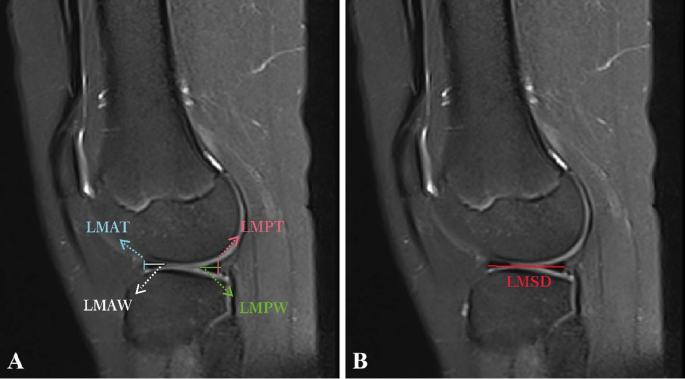

On the coronal images of the T2WI sequence, the measurements were as follows: the lateral meniscal body thickness (LMBT), the lateral meniscal body width (LMBW), the medial meniscal body thickness (MMBT), the medial meniscal body width (MMBW), the tibial plateau width (TPW), the lateral tibial plateau width (LTPW), the medial tibial plateau width (MTPW), the tibial intercondylar ridge width (TIRW), and the tibial intercondylar ridge height (TIRH) (Fig. 2). On the sagittal images of the T2WI sequence, the measurements were as follows: the lateral meniscal anterior horn thickness (LMAT), the lateral meniscal anterior horn width (LMAW), the lateral meniscal posterior horn thickness (LMPT), the lateral meniscal posterior horn width (LMPW), the lateral meniscal sagittal diameter (LMSD), the medial meniscal anterior horn thickness (MMAT), the medial meniscal anterior horn width (MMAW), the medial meniscal posterior horn thickness (MMPT), the medial meniscal posterior horn width (MMPW), and the medial meniscal sagittal diameter (MMSD) (Figs. 3 and 4). Although the study performed measurements on T2WI, the researchers reviewed T1WI and fat-suppressed sequences to confirm meniscal boundaries and to exclude abnormalities.

Measurements of the lateral meniscus in sagittal position of MRI.